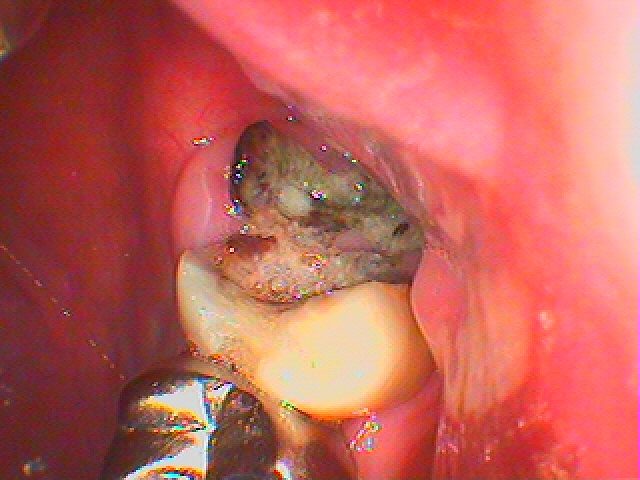

7番は大きく虫歯となり歯が半分になっています。

8番は歯なのかどうかも分かりにくいくらい保存不能の状態です